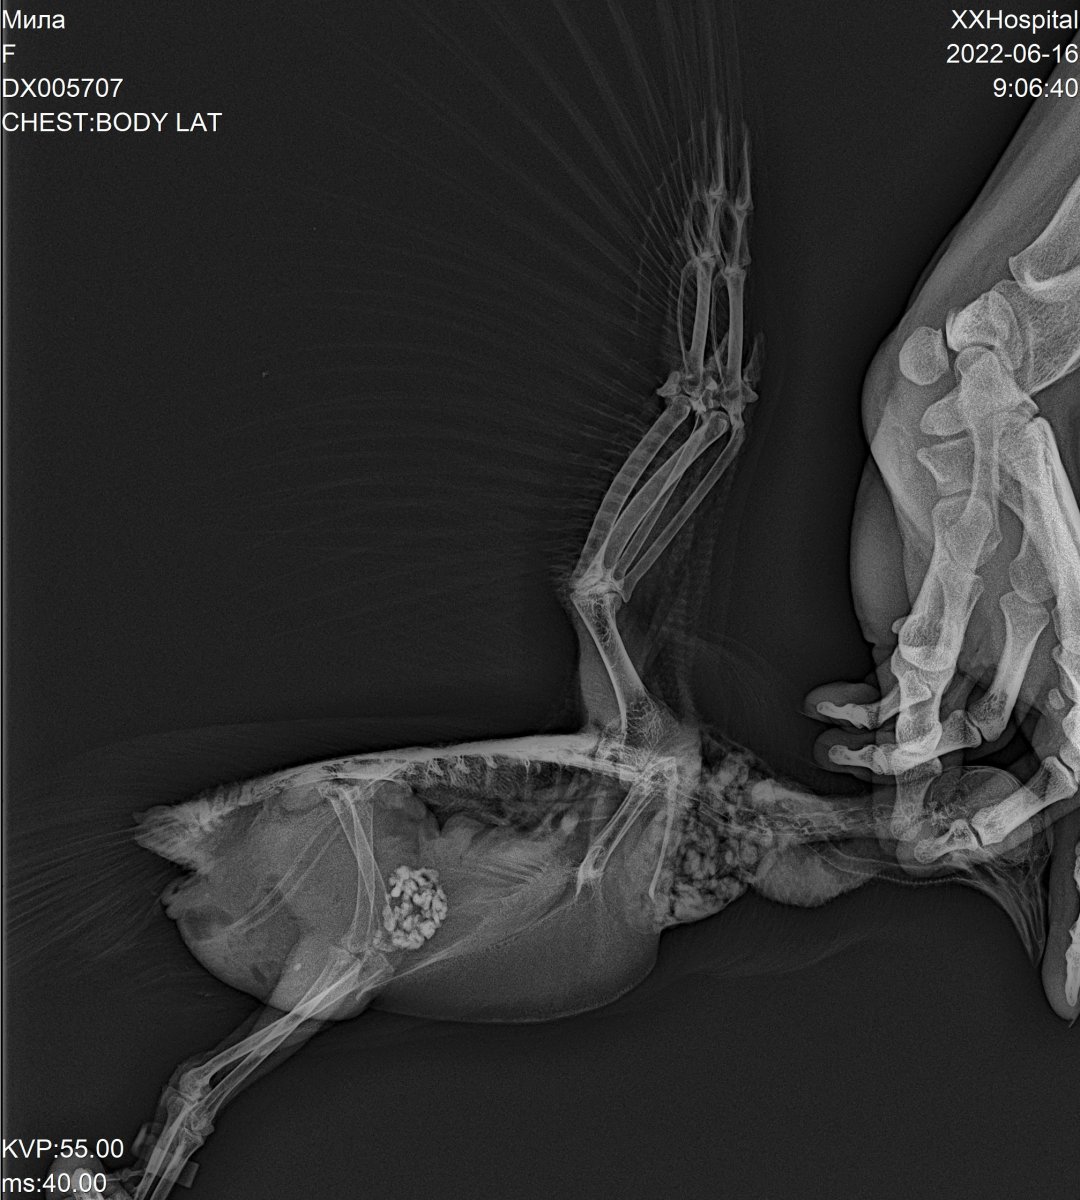

Zosia Опубликовано 19 июня, 2022 #93 Опубликовано 19 июня, 2022 (изменено) У птицы поликистоз. Преднизолон обязательно, ригевидон обязательно, и хорошо бы вот эти Обь екты, точнее материал из серединки, на микотическое исследование. Такие денатурированные кисты встречала у птицы с аспергиллезом яичника. Вот пример https://public.fotki.com/Shemlik/bc6ed/9fa0.html Изменено 19 июня, 2022 пользователем Zosia

Аделин Опубликовано 23 июля, 2022 #132 Опубликовано 23 июля, 2022 Все-таки, если Зося писала 19.06.2022 в 18:22, Zosia сказал: и хорошо бы вот эти Обь екты, точнее материал из серединки, на микотическое исследование. видимо, подозревала, что кисты могут иметь грибковую природу. Причины кист яичника бывают разные. У человека грибковые не перечислены. Может, у птиц по- другому. Возможно, причина воспаления кист - одна, а проблемы с жкт- уже симптом, и ножка, может, тоже симптом, пережатые сосуды. Здесь бы снимок. 1